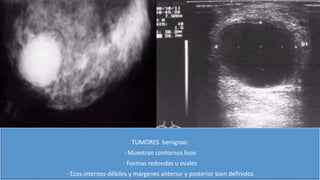

TUMORES benignas:

- Muestran contornos lisos

- Formas redondas u ovales

- Ecos internos débiles y márgenes anterior y posterior bien definidos

TUMORES benignas: - Muestrancontornos lisos - Formas redondas u ovales - Ecos internos débiles y márgenes anterior y posterior bien definidos